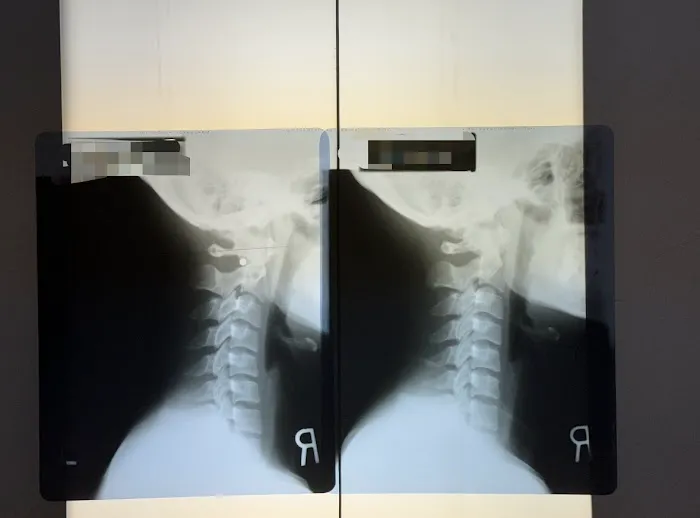

Thorough Diagnostic Assessments: A hallmark of their service is the initial in-depth assessment, including taking an X-ray "before starting any treatment to pinpoint exactly what needed to be fixed." This detailed approach ensures that treatments are precise and targeted to the root cause of the patient's condition.

Dr. Park's Exceptional Skill and Meticulous Approach: The most significant highlight is the expertise of Dr. Park, consistently lauded as "the Best!" Patients appreciate his "very thorough" initial assessment, including X-rays, to "pinpoint exactly what needed to be fixed." This detail-oriented approach ensures that treatments are incredibly precise and effective, leading to significant and lasting improvements, even for complex injuries.

Firstly, the expertise of Dr. Park, frequently lauded as "the Best!" and a "skilled, caring, and detail-oriented" practitioner, is a major draw for locals. In a city where health and wellness are highly prioritized, finding a chiropractor who conducts a "very thorough" initial assessment, including X-rays, to "pinpoint exactly what needed to be fixed," ensures that patients receive precise and effective care. This level of diagnostic accuracy is crucial for treating complex conditions like serious back injuries or shoulder dislocations from accidents, leading to faster and more complete recoveries.

Apr 16, 2025 · Leo MiguelExceptional Chiropractic Care – Dr. Park is the Best!I had a shoulder dislocation and a misaligned spine due to an accident, and Dr. Park at Yonsei Chiropractic truly helped me recover. From the beginning, he was very thorough, taking an X-ray before starting any treatment to pinpoint exactly what needed to be fixed. He explained everything clearly, which made me feel confident and reassured throughout the process.The adjustments were precise, and I could feel the improvement after each visit. Now, my shoulder and spine feel so much better. The clinic is clean, well-organized, and has a welcoming atmosphere. The staff is also very friendly and professional.If you’re looking for a chiropractor who is skilled, caring, and detail-oriented, I highly recommend Dr. Park. Five stars all the way!

Mar 07, 2025 · Mijeong KimThis clinic is life-changing! I came here following a car accident with neck and back pain. The entire process was seamless, from completing paperwork to getting X-rays. Every question I had was thoroughly answered, making me feel well-informed and cared for. The Dr. Park is highly professional and kind, and the treatment room is clean, inviting, and enhanced by soothing classical music. After almost 3 months of sessions, I am sleeping better and my neck and back pain have subsided thanks to Dr. Park. Scheduling is flexible, and they even validate parking, which is a great bonus. I couldn’t be happier with my experience—10/10, highly recommend!Update: I recently completed my treatment at this clinic, and I truly wish I had more sessions! The chiropractor was fantastic—extremely knowledgeable, professional, and kind. Throughout my treatment, I made great progress; my neck pain has significantly improved, and I can finally sleep through the night again. The entire experience, from the smooth intake process to the welcoming atmosphere with soothing classical music, was outstanding. Scheduling was always flexible, and the fact that they validate parking was a great convenience. I highly recommend this clinic to anyone in need of chiropractic care—10/10!

Mar 22, 2025 · Ruty De Los SantosI have been seeing Dr. Park almost 8 months now for severe back and buttock pain from bulging disks and SI joint inflammation. Dr. Park took X rays from my head to the sacrum, and she found that my neck is the source of all my spine problems. I also went to the UCLA spine center and did MRI during the chiropractic treatment.The UCLA MD prescribed physical therapy and said ok to continue to do chiropractic treatment.The first couple of months, I was unsure if this bone adjustment was really working on my pain.However, about 3 months later, I noticed that my back pain improved, and I was able to sit and stand longer. Now, I visit Yonsei chiropractic clinic every other week and will continue monthly for maintenance therapy.